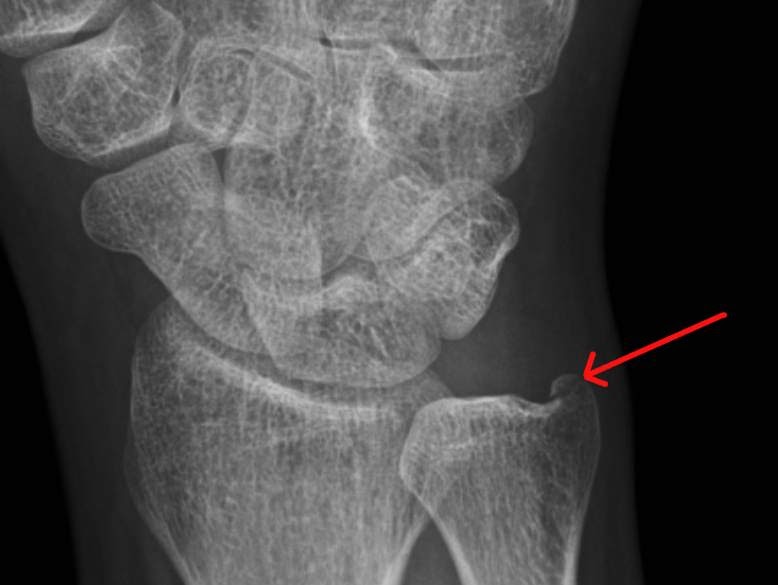

RiT radiology Isolated Ulnar Styloid Process Fracture What Does Remote Fracture Mean Distal radius fracture (drf) is a common fracture of the upper extremity. A fracture means that a bone has been broken, either partially or completely, due to excessive force or stress. Fractures of the radius and ulna are the most common fractures of the upper extremity, with distal fractures occurring more often than proximal fractures. A fracture of the distal. What Does Remote Fracture Mean.